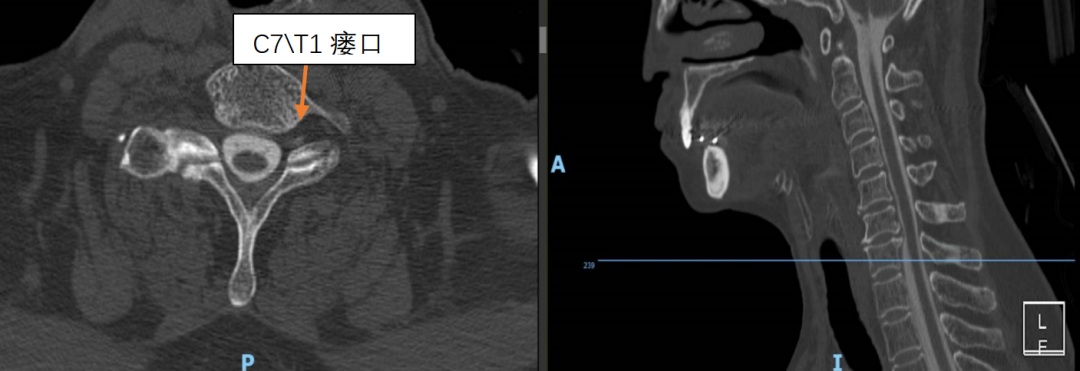

为精准定位“漏点”,刘伟主任医疗团队为靳女士安排了腰椎穿刺测压和全脊柱核磁水成像检查。结果证实了诊断:颅压低至68mmH₂O(正常约为80-180mmH₂O),进一步行腰大池CT造影剂清晰地显示,漏口就隐藏在颈7/胸1和胸1/2这两个节段。

术前术后影像对比

术前影像